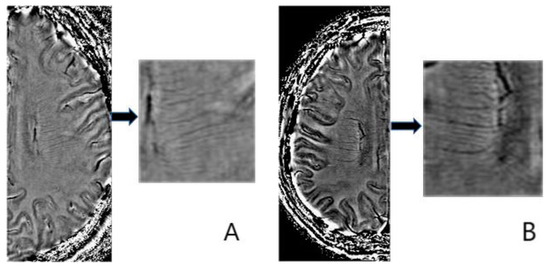

2.5. Deep Medullary Veins Score

- Zhang, R.; Zhou, Y.; Yan, S.; Zhong, G.; Liu, C.; Jiaerken, Y.; Song, R.; Yu, X.; Zhang, M.; Lou, M. A Brain Region-Based Deep Medullary Veins Visual Score on Susceptibility Weighted Imaging. Front. Aging Neurosci. 2017, 9, 269. [Google Scholar] [CrossRef]